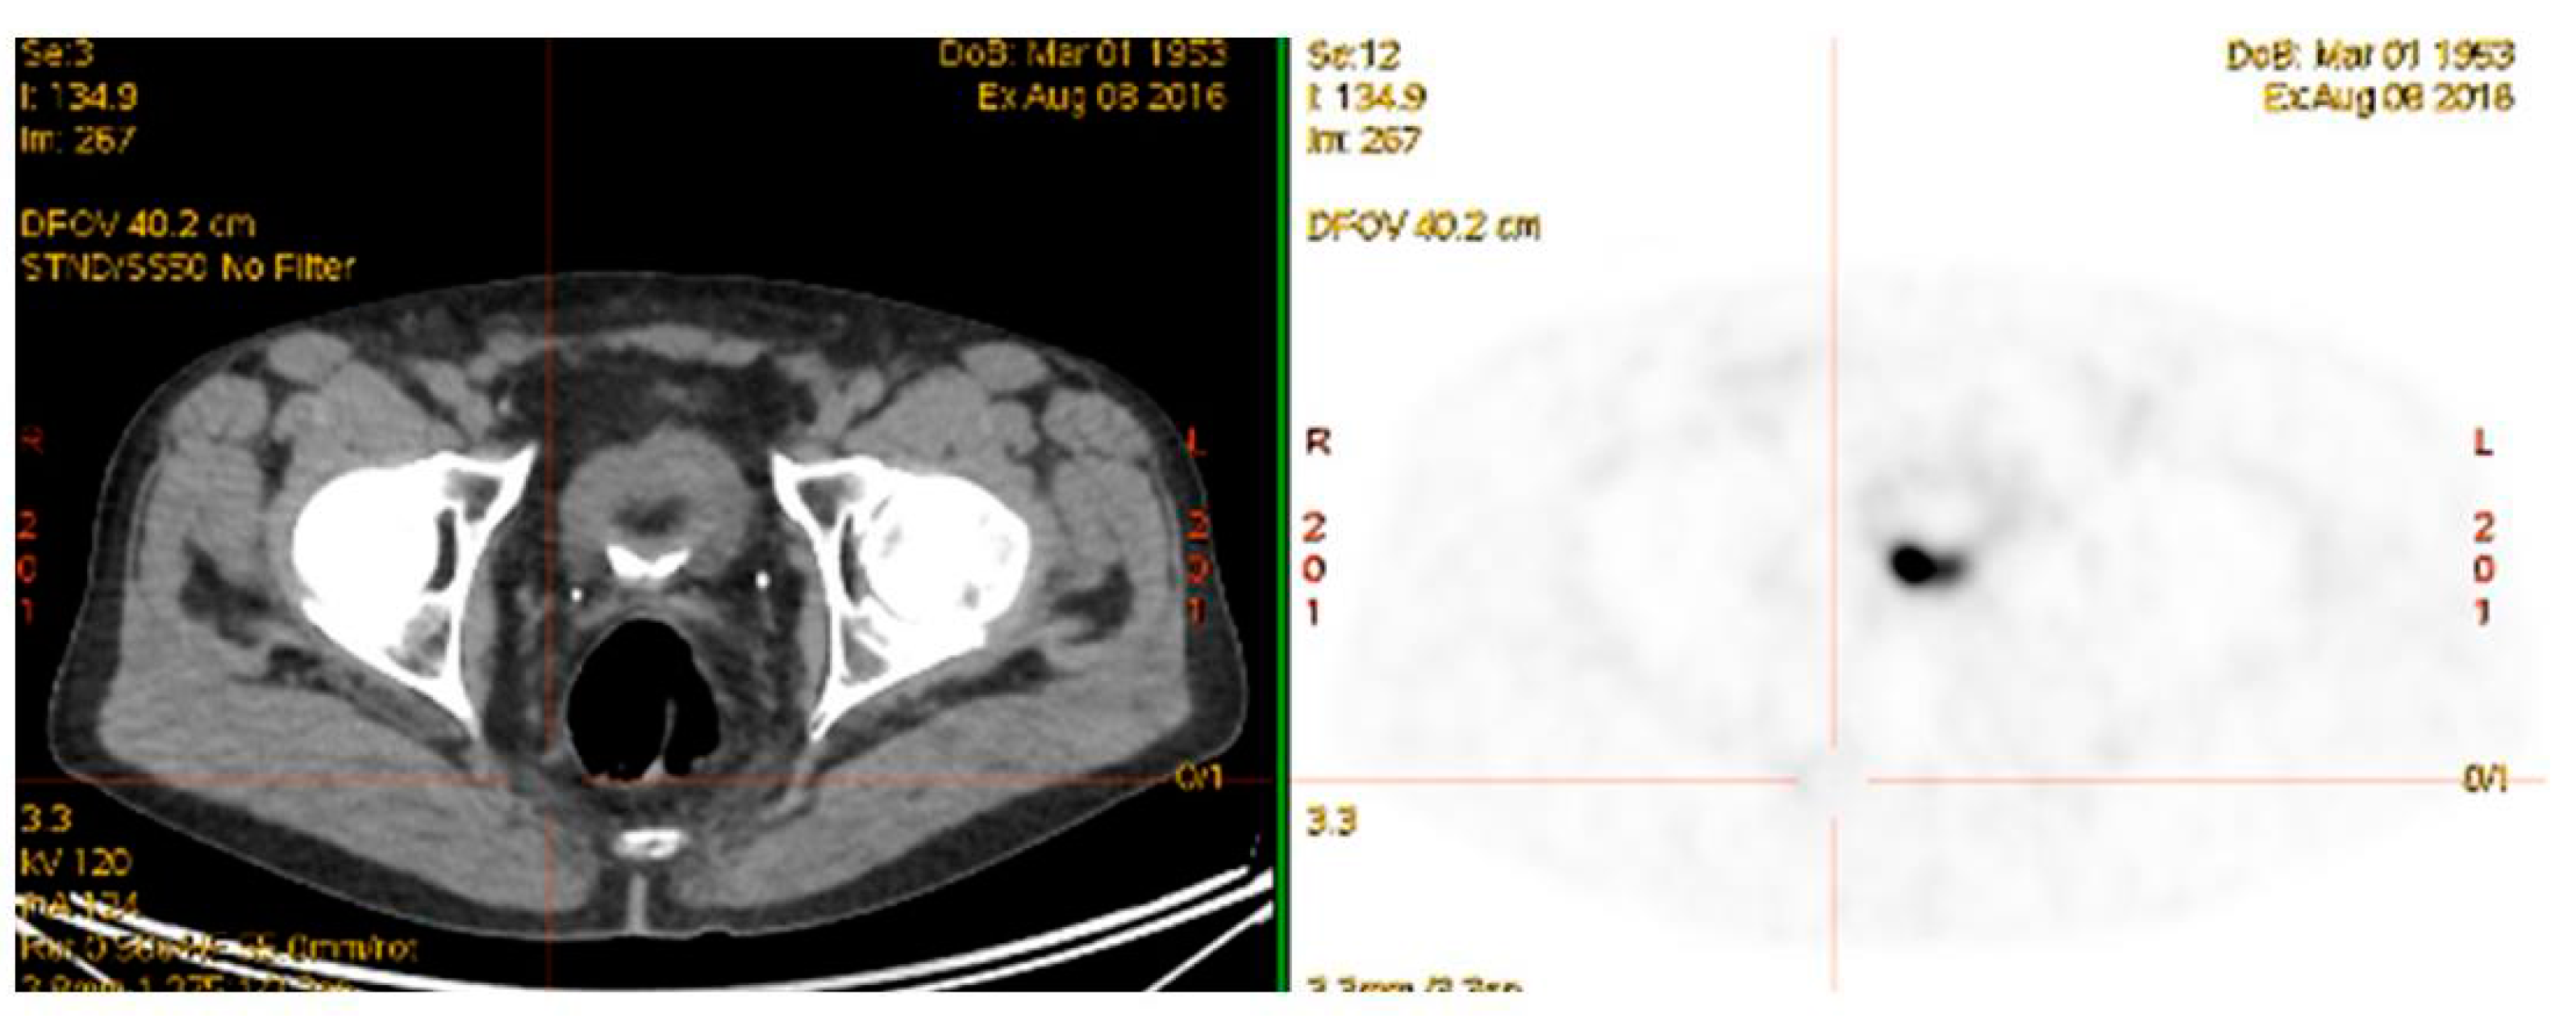

68Ga-PSMA PET/CT has been used over the last 4–5 years in its theranostic capacity to guide therapy using the labelled therapeutic radiopharmaceutical 177Lu-PSMA (Figure 6). This targeted radiopeptide therapy has been shown to decrease PSA levels, objectively decrease tumor volumes and tumor activity and improve progression free survival in 40–70% of mCRPC patients who have failed previous treatment modalities including chemotherapy [2,115,116,117,118,119,120]. This has been shown to be a well-tolerated treatment with minimal acute or medium term side-effects, similar to our experience with 177Lu-DOTATATE in NET’s. More recently targeted alpha therapy 225Ac-PSMA has also been shown, in much smaller studies, to also decrease PSA levels, tumor volumes and tumor activity in patients who have failed 177Lu-PSMA [3,121]. A more pronounced effect on salivary gland function has been identified following 225Ac-PSMA therapy. Longer term toxicities, if any, are yet to be determined.

Figure 6.

Before (top) and after (bottom) 3 cycles of 177Lu-PSMA therapy for progressive metastatic castrate resistant prostate cancer. [X axis—time in months/; Y axis—PSA (μg/L)].